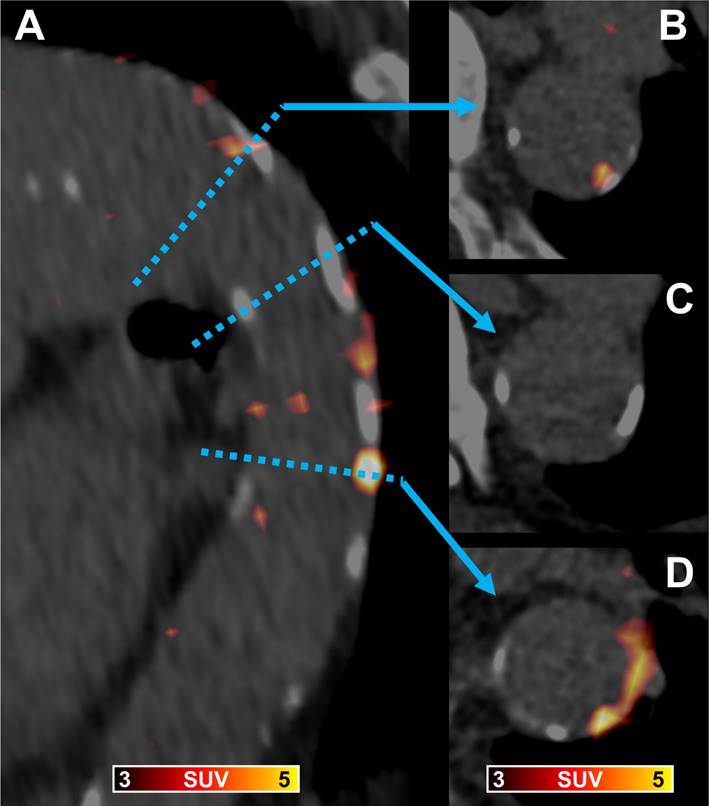

With all patients showing PentixaFor+ sites, 4/65 (6.1%) patients were rated PentixaFor+/CAP-, and the remaining 61/65 (93.8%) PentixaFor+/CAP+ in a per-patient analysis (Figure 1).

Figure 1

[68Ga]Ga-PentixaFor PET/CT in a 89-year old man showing a fused parasagittal image reconstruction of the aortic arch and the descending thoracic aorta (A) and three paraaxial slices (B trough D) at levels indicated by the blue dotted line and arrows. In (B) arterial wall radiotracer uptake is partially co-localized with calcification, in (C) vessel wall calcification without radiotracer uptake is shown, and in (D) vessel wall radiotracer uptake without corresponding calcification and calcification without co-localized radiotracer uptake is visible.

On a per-segment level, 335/455 segments (73.6%) were PentixaFor+, and 299/455 (65.7%) segments CAP+, with 228/455 (50.1%) PentixaFor+/CAP+ segments, and 107/455 (23.5%) PentixaFor+/CAP- segments. 71/455 (15.6%) segments were PentixaFor-/CAP+, and 49/455 (10.8%) segments were rated negative for both, [68Ga]Ga-PentixaFor uptake, and CAP.

On a per-lesion level, 385/1292 (29.8%) PentixaFor+ sites were also CAP+. This amounts to 26.9% (385/1431) of all CAP+ sites. Correlative analyses showed no significant correlations between the number of PentixaFor+ sites or PentixaFor+ site TBR with number of CAP+ sites, calcification circumference score, and CAP thickness (number of PentixaFor+ sites: r ≤ 0.18, P ≥ 0.14; PentixaFor+ TBR: r ≤ 0.08, P ≥ 0.54).